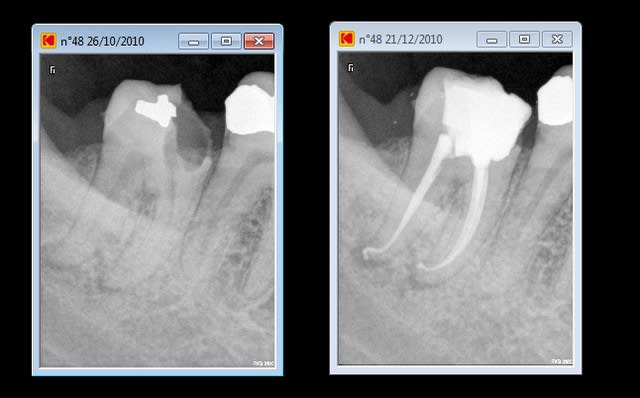

pourquoi l'endo au fait (nécrose racine distale de 46)

préparation Mtwo et j'aime bien .